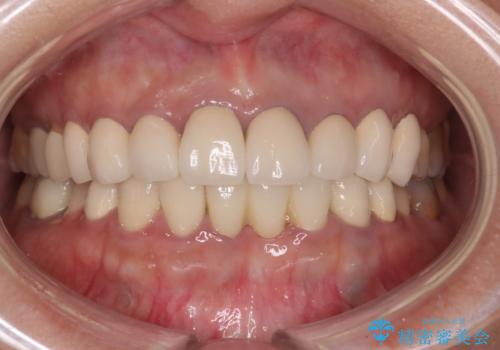

前歯が一本取れた オールセラミックブリッジによる補綴治療

- 約38万円費用は治療当時の料金となります

抜歯をしているため、その部位の治癒を待ってからブリッジを装着するので、2-3か月ほど治療期間を必要としました。